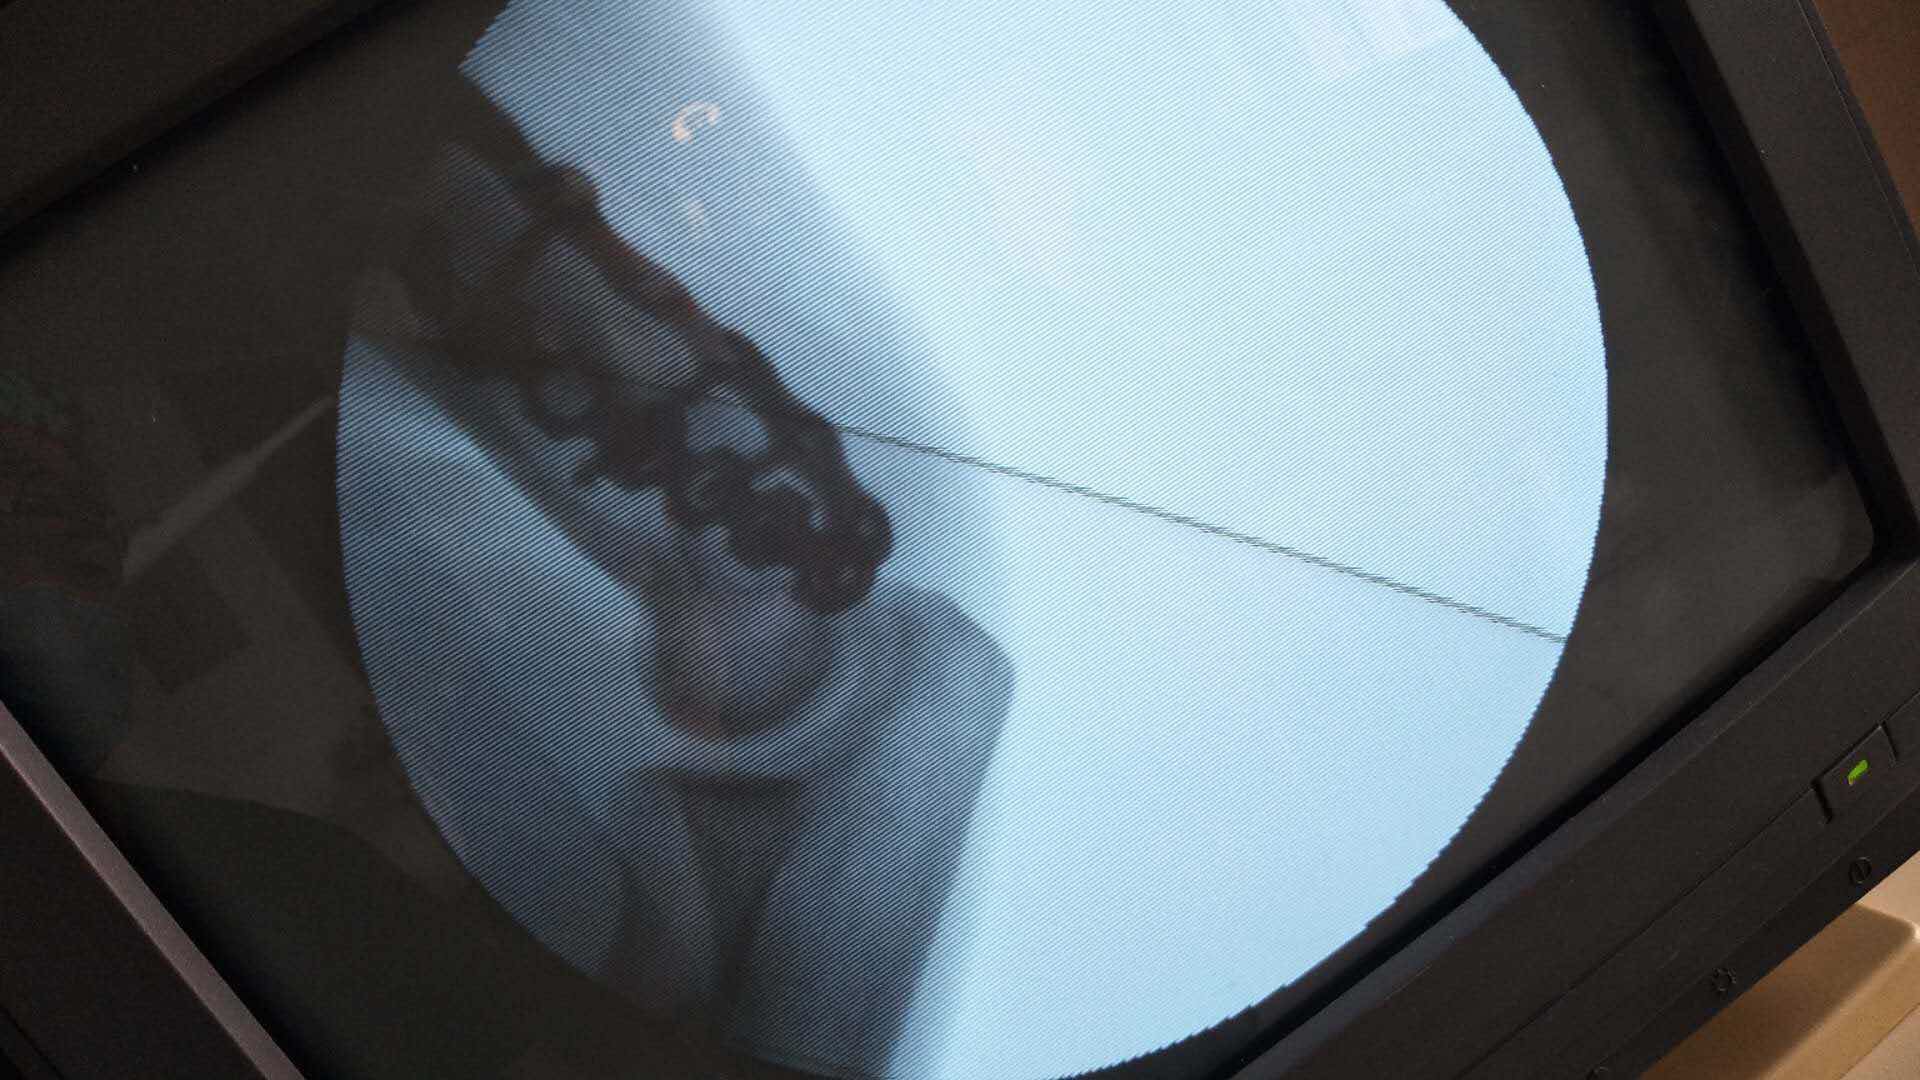

肱骨远端骨折(切复双钛板内固定)

摔伤后右肘部肿胀,畸形,活动受限2小时入院。既往身体健康,无特殊不良嗜好。从事健身教练工作数年。

生命体征平稳,心肺复未见异常。右上臂肿胀明显,畸形,局部皮色发红,皮温高,压痛及纵叩痛阳性,可及骨檫音及骨檫感,异常活动,末梢血运感觉正常。

诊断肱骨远端骨折在臂丛麻醉下行切复内固定术,术后抗炎,消肿等处理。